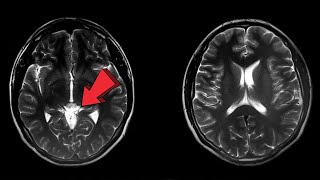

First Brain Scan of Dying Man Reveals a Unexpected Secret !

First Brain Scan of Dying Man Reveals a Unexpected Secret ! First scan of a dying human brain shows life flashes before eyes

First scan of a dying human brain shows life flashes before eyes Brain Scan : First Brain scan of Dying person | What thought come in the mind of a dying man

Впервые зафиксировали активность мозга умирающего человека First-Ever Scan of a Dying Brain Shows Life May Flash Before Eyes

First-Ever Scan of a Dying Brain Shows Life May Flash Before Eyes First Scan of the Dying Brain Reveals a "Last Recall"

First Scan of the Dying Brain Reveals a "Last Recall" Dying Man's Brain Scan Suggests Life Could Flash Before Your Eyes | NBC4 Washington